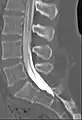

![]() Myelogram showing arachnoiditis in the lumbar spine. | |